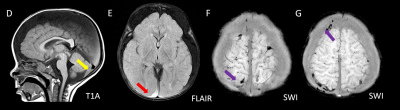

- A) Bilateral serebral konveksitede subdural higroma

- D) Posteriyor fossada subdural hemoraji

- E) Subdural hematohigroma ile uyumlu yoğun içerikli bileşenler

- F) Verteks düzeyinde lolipop/iribaş (tadpole) işareti

- G) Verteks düzeyinde köprü ven trombozuna/yaralanmasına ait duyarlılık artefaktı

- H) Nukal bağda yaralanma lehine T2 sinyal artışı

- I) Sağ bulbus okulide retinal hemoraji

Görüntüleme Bulguları

- İstismara bağlı kafa travmasında en sık saptanan radyolojik bulgular:

- Subdural hematom: En sık görülen radyolojik bulgudur, vakaların %83-90’ında saptanır. Genellikle bilateraldir ve farklı yaşlarda hemorajik elemanlar içerir.

- Subdural higroma: Araknoid yırtıklara bağlı gelişir. Köprü ven yaralanması ile birlikte olduğunda hemorajik bileşenler içerebilir (hematohigroma).

- Köprü ven trombozu: Manyetik duyarlılık görüntülemede, kortikal ven trasesinde duyarlılık artefaktı olarak ya da “lolipop” ve “iribaş” (tadpole) işareti şeklinde görülür. Vakaların yaklaşık %30-45’inde saptanır.

- Spinal yaralanmalar : Sanılandan daha yaygındır ve olguların yaklaşık %30-40’ında görülür. Genellikle gözden kaçar. En sık saptanan bulgular servikal spinal bağ yaralanmaları ve spinal subdural hematomdur.

- Retinal hemorajiler vakaların yaklaşık %85’inde görülür. Bilateral çok sayıda kanama olması istismar ilişkili yaralanma açısından kuvvetli şüphe oluşturmalıdır. Tanı temelde muayene bulguları ile konulur; ancak manyetik duyarlılığa dayalı görüntüleme (SWI) ve difüzyon görüntüleme de yararlı olabilir.